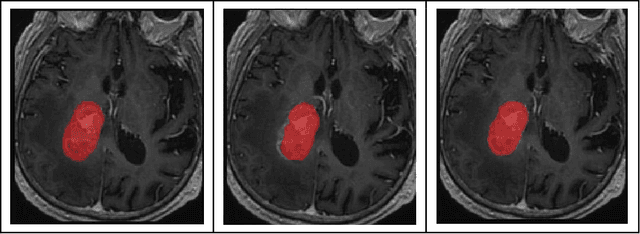

Abstract:This paper introduces Med-DDPM, an innovative solution using diffusion models for semantic 3D medical image synthesis, addressing the prevalent issues in medical imaging such as data scarcity, inconsistent acquisition methods, and privacy concerns. Experimental evidence illustrates that diffusion models surpass Generative Adversarial Networks (GANs) in stability and performance, generating high-quality, realistic 3D medical images. The distinct feature of Med-DDPM is its use of semantic conditioning for the diffusion model in 3D image synthesis. By controlling the generation process through pixel-level mask labels, it facilitates the creation of realistic medical images. Empirical evaluations underscore the superior performance of Med-DDPM over GAN techniques in metrics such as accuracy, stability, and versatility. Furthermore, Med-DDPM outperforms traditional augmentation techniques and synthetic GAN images in enhancing the accuracy of segmentation models. It addresses challenges such as insufficient datasets, lack of annotated data, and class imbalance. Noting the limitations of the Frechet inception distance (FID) metric, we introduce a histogram-equalized FID metric for effective performance evaluation. In summary, Med-DDPM, by utilizing diffusion models, signifies a crucial step forward in the domain of high-resolution semantic 3D medical image synthesis, transcending the limitations of GANs and data constraints. This method paves the way for a promising solution in medical imaging, primarily for data augmentation and anonymization, thus contributing significantly to the field.

Abstract:Semantic segmentation of medical images with deep learning models is rapidly developed. In this study, we benchmarked state-of-the-art deep learning segmentation algorithms on our clinical stereotactic radiosurgery dataset, demonstrating the strengths and weaknesses of these algorithms in a fairly practical scenario. In particular, we compared the model performances with respect to their sampling method, model architecture, and the choice of loss functions, identifying the suitable settings for their applications and shedding light on the possible improvements.

Abstract:Stereotactic radiosurgery (SRS), which delivers high doses of irradiation in a single or few shots to small targets, has been a standard of care for brain metastases. While very effective, SRS currently requires manually intensive delineation of tumors. In this work, we present a deep learning approach for automated detection and segmentation of brain metastases using multimodal imaging and ensemble neural networks. In order to address small and multiple brain metastases, we further propose a volume-aware Dice loss which optimizes model performance using the information of lesion size. This work surpasses current benchmark levels and demonstrates a reliable AI-assisted system for SRS treatment planning for multiple brain metastases.